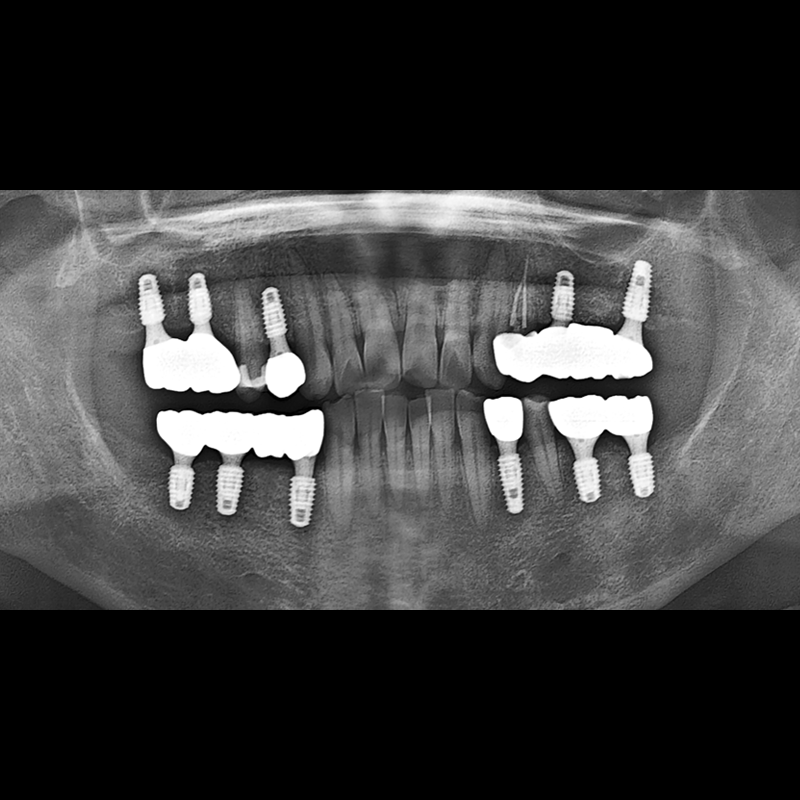

BEFORE AFTER

インプラント手術事例 2025.12.10

欠損した歯の部分と、生かしにくい歯の位置にインプラントを植立しました。